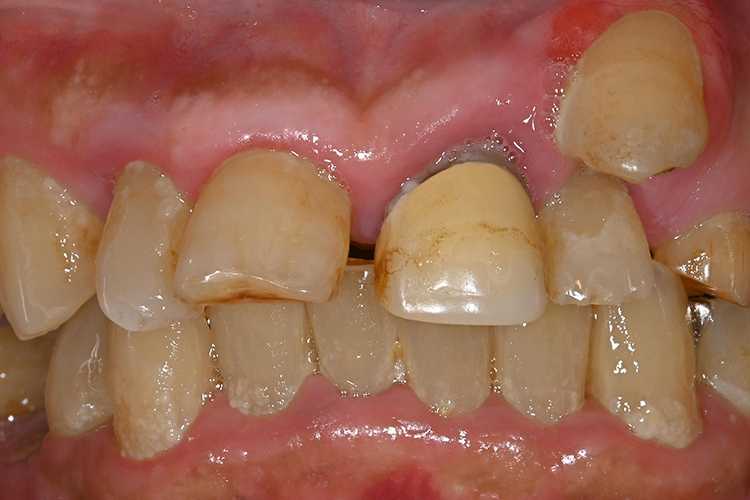

この患者様は、口腔内全体において重度の歯周病が生じており、歯磨き指導、クリーニング、Flap手術等を行ったが、歯周ポケットが深すぎるためブルーラジカル適用症例と診断し、施術を行いました。

施術前のレントゲンと口腔内写真です。施術前にプラークの除去を行ってから、施術します。

この患者様は、スケーリングより歯周ポケットが6mm以上ある患者様で患者様ご本人も歯周病になりかけている自覚がありました。

また、口臭も気になされていましたので、ブルーラジカルの適用症例と判断し、施術を行いました。

施術前のレントゲンと口腔内写真です。